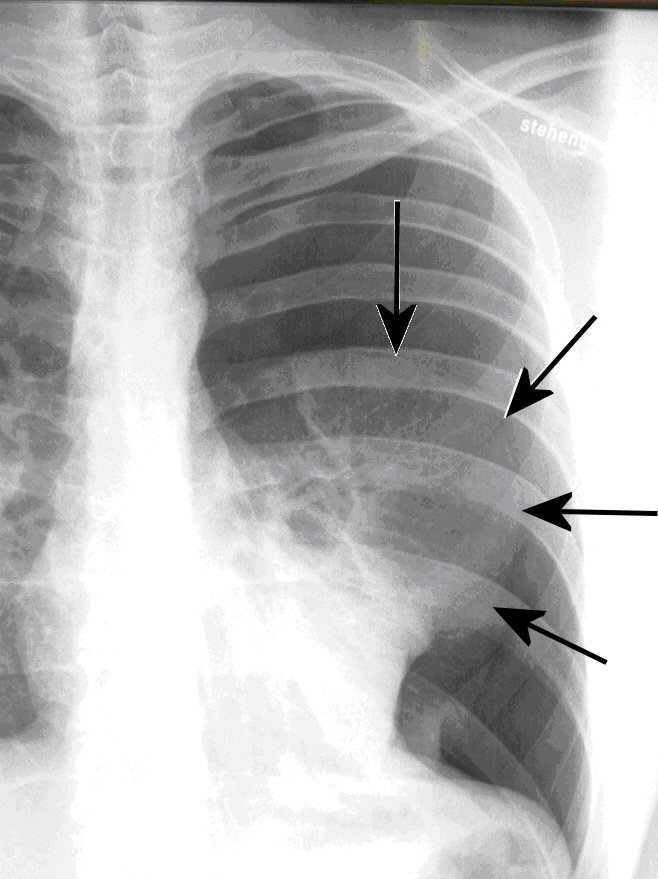

| Abb. 1: Spontanpneumothorax (Lungenkollaps) bei einem 25-jährigen schlanken Mann (die Pfeile zeigen den Rand der kollabierten Lunge) |